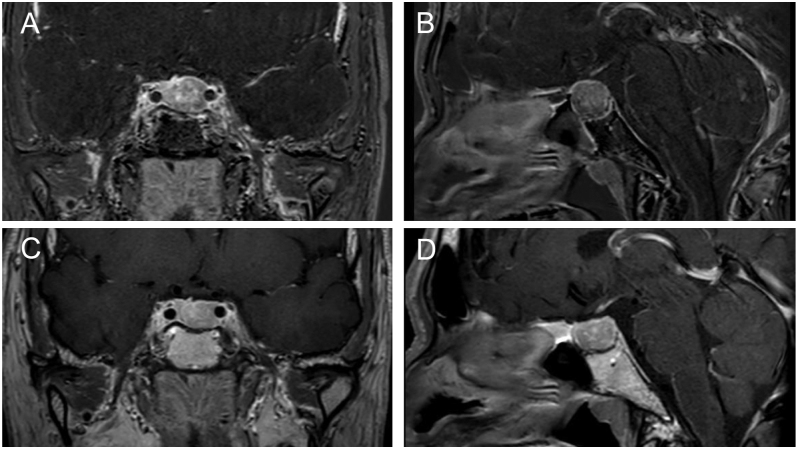

Summary: We present the case of a 51-year-old man who was referred to our hospital due to abnormal thyroid function tests. Laboratory evaluations showed elevated serum free (F) T3 and free (F) T4 levels (9.05 pg/mL and 4.21 ng/dL, respectively), with a normal serum thyroid-stimulating hormone (TSH) level of 1.49 μIU/mL, indicating central hyperthyroidism. An 18 × 17 × 14 mm T1-weighted hypointense tumor was found on the left side of the pituitary gland, with low contrast enhancement during a cranial MRI. The TRH stimulation test revealed no TSH response. The administration of a single dose of octreotide reduced TSH levels. Following these findings, the patient was clinically diagnosed with a TSH-producing pituitary tumor (TSHoma). The patient was directed to our hospital's neurosurgery department for pituitary surgery and began preoperative treatment with lanreotide autogel (90 mg, subcutaneous injection). Four days after administration, FT3 and FT4 levels returned to normal. Seven days after administration, an MRI revealed a 50% reduction in tumor volume. Endoscopic pituitary surgery was performed 15 days after the initial administration and resulted in complete tumor resection. A histopathological examination confirmed the presence of a TSH-producing pituitary neuroendocrine tumor. Postoperatively, FT3 and FT4 levels stayed within the normal ranges. This case demonstrates how a single dose of lanreotide autogel not only normalized thyroid hormone levels but also resulted in rapid shrinkage of the pituitary tumor in TSHoma.

Learning points: Preoperative treatment with somatostatin analogs for TSH-producing pituitary adenomas (TSHomas) aims to control thyroid function, preventing thyroid storm during surgery, and to reduce tumor size. We report a case of a TSHoma treated preoperatively with a single subcutaneous injection of lanreotide autogel (LAN-ATG). In this patient, thyroid function normalized and significant tumor shrinkage was observed within 1 week of LAN-ATG administration. This case demonstrates that significant therapeutic effects can be achieved within days after a single injection of LAN-ATG. This approach could facilitate earlier surgical intervention, potentially improving patient outcomes and optimizing preoperative management strategies.